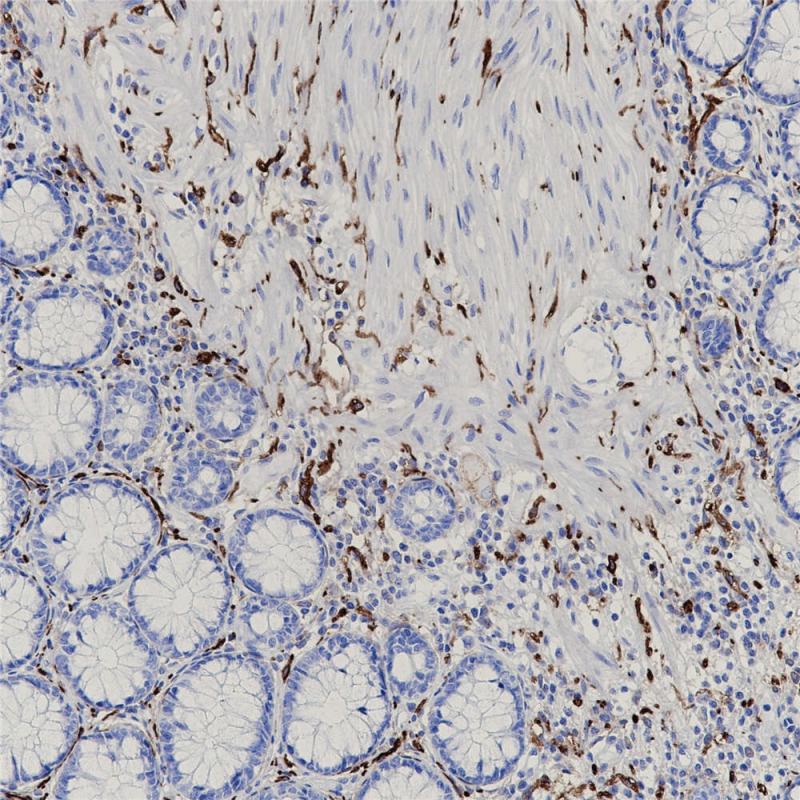

Podoplanin 重组兔单克隆抗体

Podoplanin主要表达于淋巴管内皮细胞、胎儿睾丸组织和睾丸生殖细胞肿瘤中,而在微血管内皮中无表达。该抗体是正常和肿瘤组织中淋巴管内皮的一种新的标记物,可与内皮细胞标记联合应用于淋巴管内皮源性肿瘤的诊断。